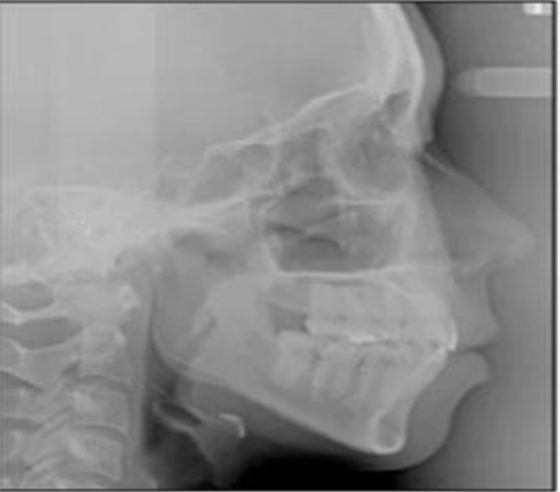

頭側(cè)分析提示為骨性安氏II類(ANB,8.4°;Wits,3.6mm),高角(SN-MP,44.9°),上頜切牙略舌傾(U1-SN,96.2°),下頜切牙略舌傾(IMPA,88。3°)(圖2;表)

治療后頭側(cè)數(shù)據(jù)提示:無明顯骨性變化(上頜SNA82.1°,下頜SNB74.9°),上頜前牙得到內(nèi)收,略舌傾,頦部前后位置無明顯改變,仍未凸面型(圖8,表)。將治療前后圖像重疊后結(jié)果如(圖8及圖9),24月后隨訪結(jié)果見圖10.